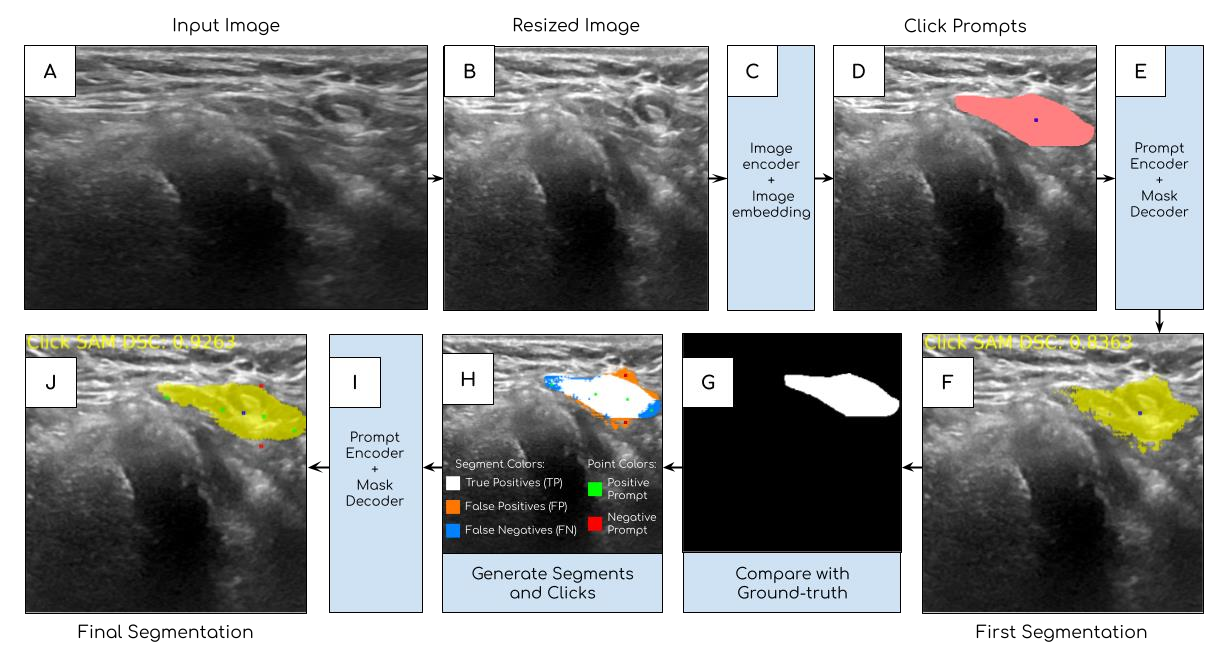

The newly released Segment Anything Model (SAM) is a popular tool used in image processing due to its superior segmentation accuracy, variety of input prompts, training capabilities, and efficient model design. However, its current model is trained on a diverse dataset not tailored to medical images, particularly ultrasound images. Ultrasound images tend to have a lot of noise, making it difficult to segment out important structures. In this project, we developed ClickSAM, which fine-tunes the Segment Anything Model using click prompts for ultrasound images. ClickSAM has two stages of training: the first stage is trained on single-click prompts centered in the ground-truth contours, and the second stage focuses on improving the model performance through additional positive and negative click prompts. By comparing the first stage predictions to the ground-truth masks, true positive, false positive, and false negative segments are calculated. Positive clicks are generated using the true positive and false negative segments, and negative clicks are generated using the false positive segments. The Centroidal Voronoi Tessellation algorithm is then employed to collect positive and negative click prompts in each segment that are used to enhance the model performance during the second stage of training. With click-train methods, ClickSAM exhibits superior performance compared to other existing models for ultrasound image segmentation.